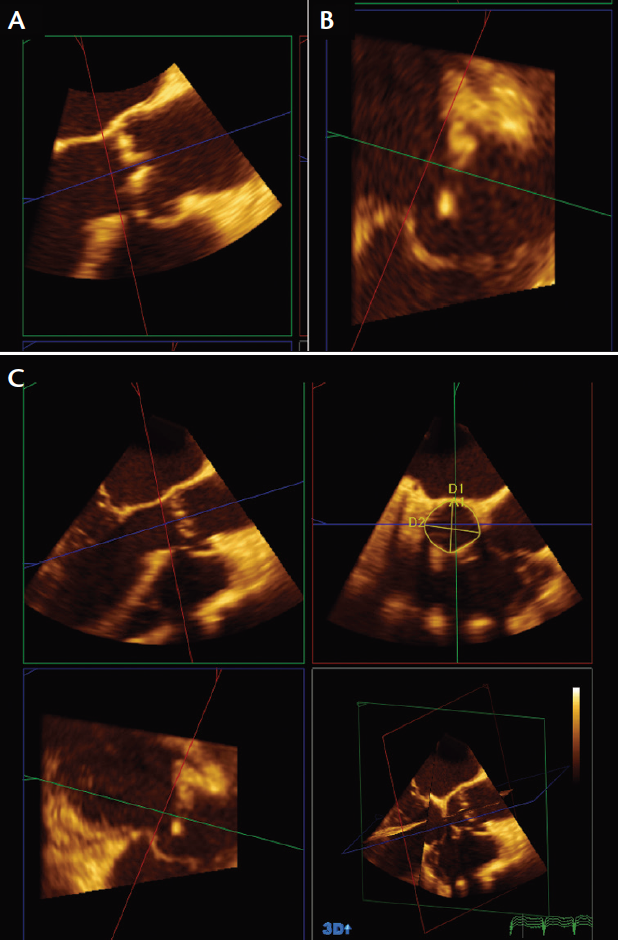

Figure 2. A 3D full-volume acquisition obtained in a long-axis view on TEE (A). The initial 2 X 2 screen that shows up when QLAB and the 3DQ function are accessed (B).

Generally, the full-volume 3D function with a one- or two-beat acquisition provides images that can give reliable annular measurements. The depth and gain must be optimized, and the TEE image has to be acquired in the long-axis view capturing the aortic valve, aortic annulus, left ventricular outflow tract (LVOT), aortic root, and part of the ascending aorta (Figure 2A). Once this image has been obtained, the commercially available QLAB software (Philips Healthcare) allows for manipulation of the 3D volumes, where a short-axis view of the annulus can be obtained by adjusting the sagittal and coronal views of the long-axis image. After opening the 3D quantification (3DQ) package in QLAB, the following steps can then be undertaken to obtain the aortic annulus:

1. Once the 3DQ package is opened, a 2 X 2 screen appears, which provides a coronal, sagittal, and transverse view of the aortic annulus (Figure 2B).

2. Scroll the image and select the mid-systolic frame.

3. Select the long-axis image and start adjusting the planes by dragging the red plane to sit right at the hinge point of the aortic valve with the blue plane perpendicular to the red plane (and parallel to the aorta) (Figure 3A).

4. Now select the red plane in Figure 3B and align it under the aortic valve, right at the hinge point of the aortic valve, then align the green plane to be perpendicular to the red plane and parallel to the aorta.

5. A short-axis image (Figure 3C) can be selected, along with the “Area” function, and the area can then be continuously traced.

6. The coronal and sagittal measurements are displayed in Figure 3C, which also shows the area and the two linear measurements.

Figure 3. After selecting a mid-systolic frame, the red plane is initially aligned just underneath the aortic valve close to the hinge points of the aortic leaflets (A). The blue plane then is aligned parallel to the aorta and perpendicular to the red plane. Similarly in this figure, the red plane is aligned underneath the aortic valve at the leaflet insertions, then the green plane is aligned parallel to the aorta and perpendicular to the red plane (B). After aligning the red, blue, and green planes, the short-axis view of the aortic annulus is obtained (C). This frame can be magnified for ease of measurement. The sagittal and coronal dimensions can also be measured from this function, along with the area. This patient had an annular dimension of 29 X 31 mm, with an area of 682 mm2.